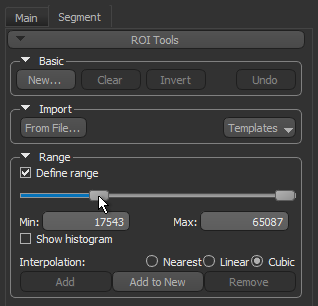

- Click the Segment tab on the left sidebar to access the ROI Tools panel.

- Select the Define range option in the Range box on the ROI Tools panel.

- Drag the left or right Range sliders to change the minimum or maximum values of the intensity range or enter the required values in the Min and Max edit boxes.

- Verify the selected range on other images in the image stack and other views of the dataset, recommended.

- Click the Add to New button to create a region of interest in which all voxels within the selected range are labeled.